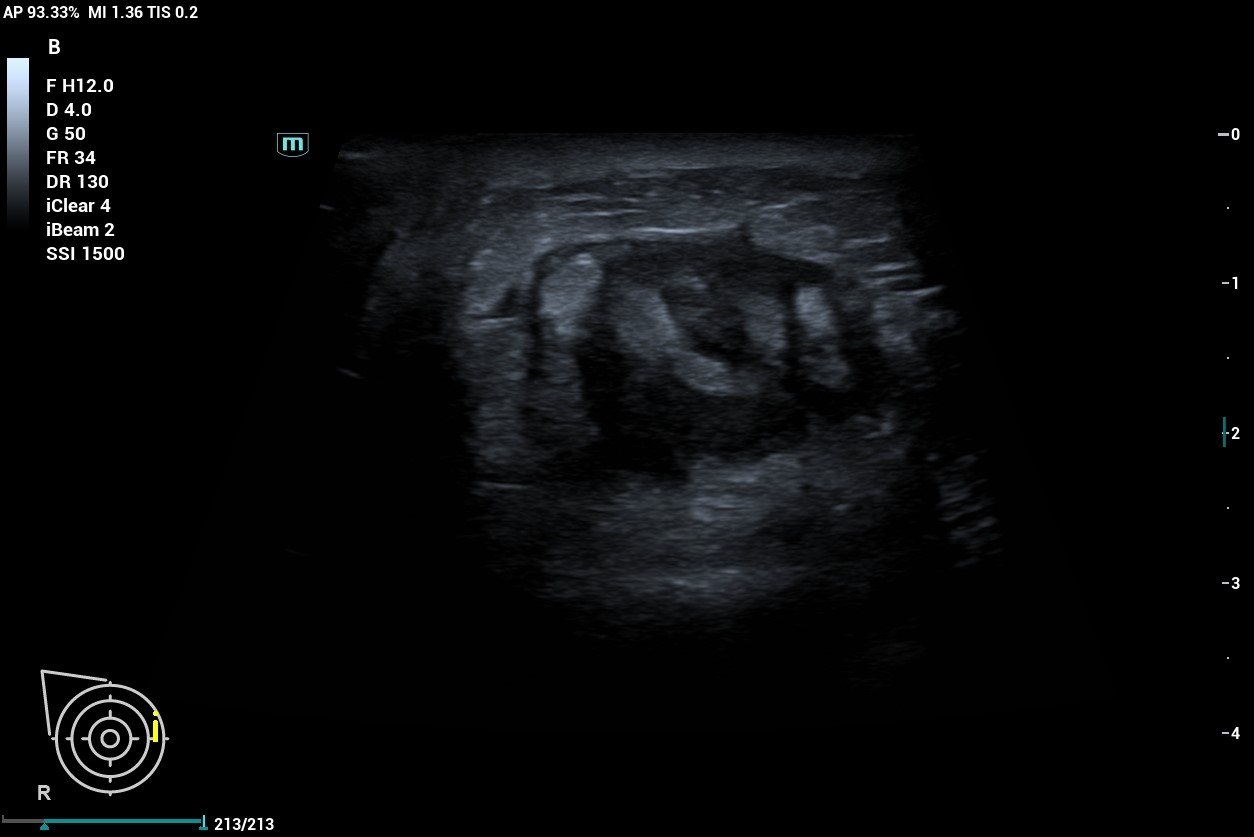

Al realizar ecografía observamos una imagen de 30 mm en cuadrantes internos de mama derecha que presenta bordes espiculados y contenido heteroecoico en su interior con áreas hipoecoicas.

Al tratarse de una lesión que presenta características de probable malignidad no solo en la exploración y anamnesis de la paciente sino a la confirmación con la ecografía, decidimos derivar a la paciente a Ginecología mediante circuito rápido, donde se confirma el diagnóstico de carcinoma ductal infiltrante de mama derecha G2, luminal B cT4bN3bM0.